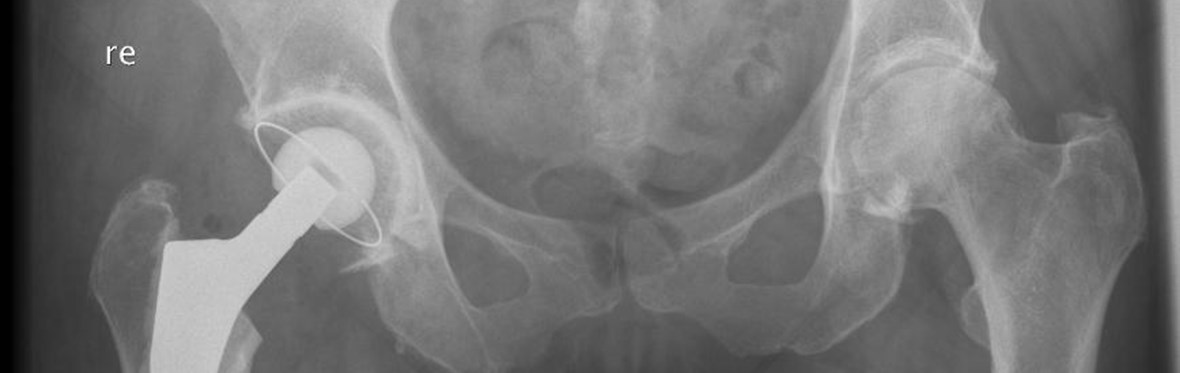

Een heupprothese bestaat doorgaans uit drie onderdelen: een steel, een kop en een kom. De steel met daarop de kop zit in het bovenbeen en kan bewegen in de kom die in het bekken zit.